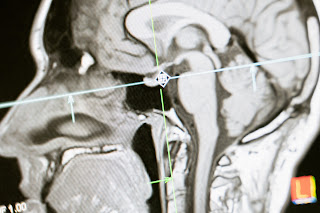

नार्को टेस्ट (Narco test) करने के लिए विशेषज्ञों की टीम तैनात की जाती है। इस टीम की देखरेख में ही सुरक्षा एजेंसियां जांच करती हैं। नार्को टेस्ट करने वाली टीम में कुछ एनेस्थिसियोलॉजिस्ट, साइकोलॉजिस्ट, टेक्नीशियन और मेडिकल स्टाफ शामिल होते हैं। आरोपी का नार्को टेस्ट (Narco test) करने से पहले फिटनेस टेस्ट किया जाता है और इस टेस्ट में पास होने के बाद ही आरोपी को नार्को टेस्ट (Narco test) के लिए ले जाया जाता है। नार्को टेस्ट (Narco test) के दौरान व्यक्ति की स्थिति को देखने के लिए तमाम तरह के मॉनिटर आदि का इस्तेमाल किया जाता है।